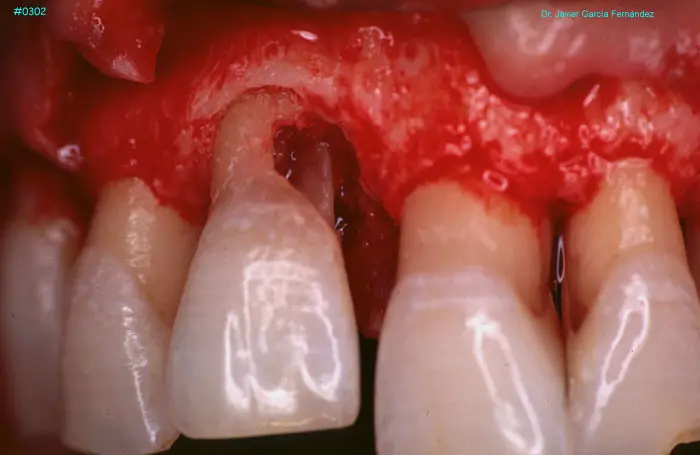

ATLAS DE CIRUGIA PERIODONTAL

image347